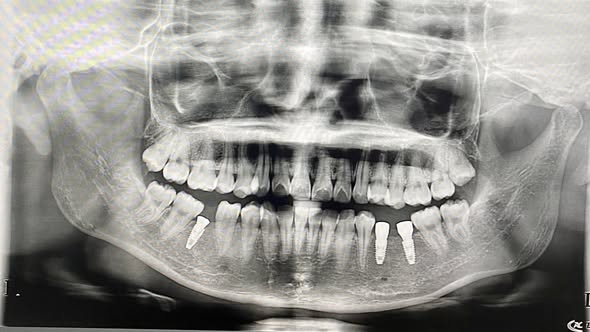

Bệnh nhân nữ 20 tuổi, bị mất 3 răng r35,36,45. Sau khi tiến hành thăm khám, chụp phim X-quang đã được đội ngũ các y bác sĩ lên kế hoạch điều trị và cấy ghép implant để thay thế những chiếc răng mất, giúp bệnh nhân đảm bảo được hiệu quả ăn nhai tuyệt đối và thẩm mỹ, tránh các biến chứng nặng nề do mất răng gây ra kịp thời